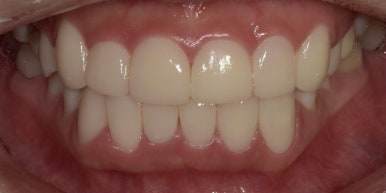

오늘 소개해드릴 환자분은 라미네이트와 크라운을 통해 치아의 모양은 물론, 배열까지 개선해 자신감을 회복하신 케이스인데요.

여러분께 치료 전후 모습을 보여드리면서 12전치 라미네이트, 크라운 케이스를 자세히 소개해드리도록 하겠습니다.

12전치 라미네이트, 크라운 치료 후

2023-07-05

1주일 후 최종적으로 보철물 제작이 완료되어 부착까지 진행해드렸는데요.

바뀐 모습 어떠신가요? 정말 몰라볼 정도로 확연하게 개선이 되었죠?

12전치 라미네이트, 크라운 치료 전후 비교

(전) 2023-06-23 (후) 2023-07-05